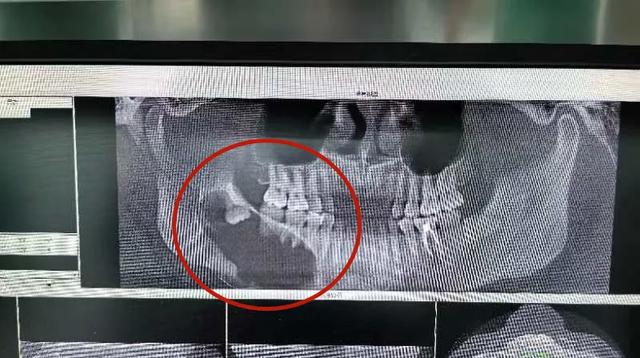

昆山市一医院口腔科立即安排

口腔颌面锥形束CT

结果提示

右下颌第一前磨牙远中至右侧下颌骨升支

见一大小约6.5cm*4.0cm 的椭圆形低密度影

囊腔压迫下牙槽神经管